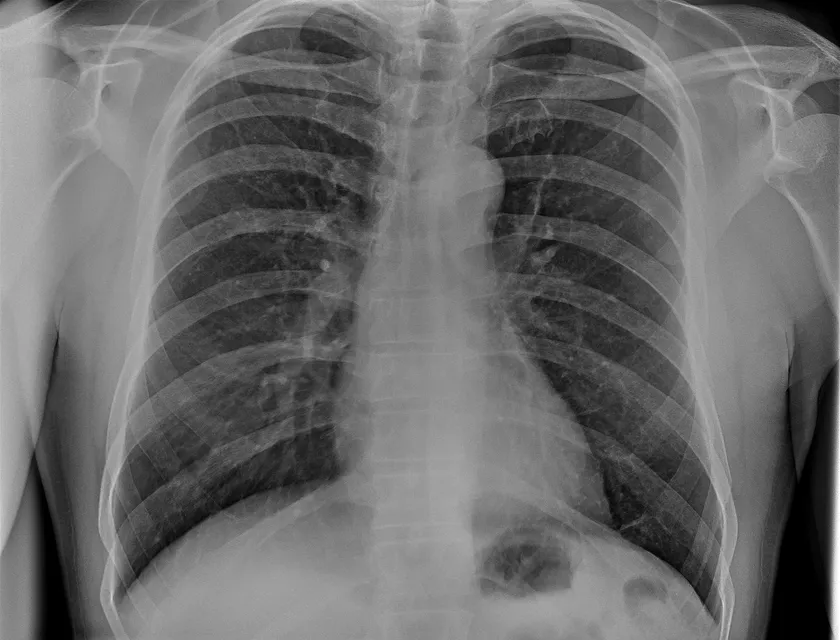

4. 高精細画像技術の展示

最大1.3kWの高出力に加え、最新のノイズ低減技術との融合により実現した高精細な画像描写をご覧いただけます。診断精度の向上に直結する画像品質の進化を、実際の撮影画像でご確認ください。

TRB 9020Hで撮影した胸部レントゲン写真

※90 kV HP mode, 1.65 mAs, 0.06 sec